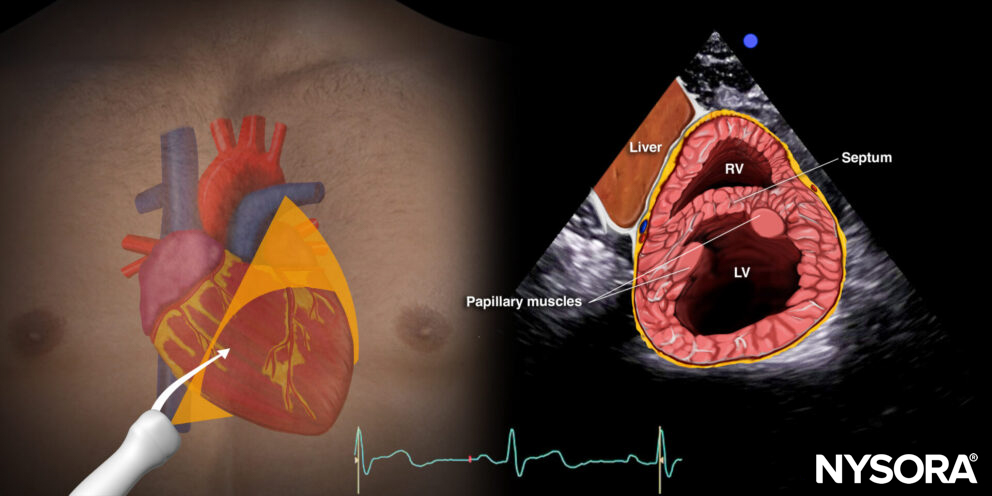

Reverse ultrasound anatomy:

Reverse Ultrasound Anatomy of the heart in the parasternal short-axis view. Right ventricle (RV), septum, left ventricle (LV), and papillary muscles.

C. Papillary muscle level or standard parasternal short-axis view: Right ventricle, left ventricle, papillary muscles (posteromedial and anterolateral papillary muscle).